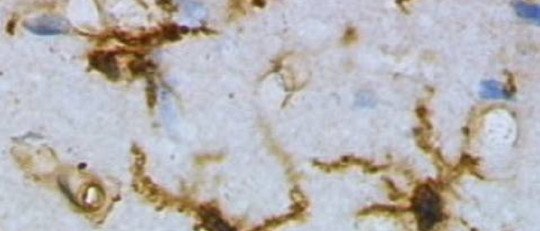

Son muchas las enfermedades y situaciones que pueden condicionar el funcionamiento de la memoria, ya que se trata de una dimensión ampliamente distribuida en el parénquima cerebral. En el presente artículo ahondaremos en las distintas formas de amnesia y en las anomalías del recuerdo o del reconocimiento, esto es, en las psicopatologías de la memoria.

Afecta sobre todo a la información episódica, o lo que es lo mismo, a los hechos vividos (mientras se mantiene la semántica, la procedimental, etc.). Suele ser una de las múltiples consecuencias derivadas de los traumatismos cerebrales, o de enfermedades demenciales que afectan a amplias regiones del sistema nervioso.

Las lesiones cerebrales en las estructuras hipocampales se han asociado consistentemente a este tipo de problemas, así como el abuso de drogas o de fármacos (alcohol, benzodiacepinas, etc.).

La amnesia infantil es aquella cuya presencia es natural durante la infancia, como resultado de un desarrollo neurológico incompleto. En el fenómeno se encuentra implicada la deficiente maduración del hipocampo, la cual impide una formación de recuerdos declarativos.